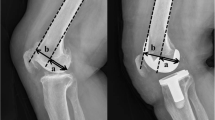

Preoperative and postoperative lateral radiograph of all 265 knee joints were used for radiological evaluation. Radiographs measurements were performed using the Picture Archiving and Communication Systems (PACS: Carestream Health, Rochester, New York, USA). Measurements were recorded to a precision of 0.1 mm and 1°. Measurements were performed using a similar method to previous authors [12, 18, 40], where PTS is the acute angle between the tibial plateau in the sagittal view, and the line perpendicular to the tibial mechanical axis (Figs. 1and 2); PCO is the perpendicular distance of the posterior-most aspect of the femoral condyle from a projection of the posterior femoral line (Figs. 1and 2); FSA is the acute angle between the cut surface of the posterior femoral condyle and the anatomical axis of the femur (Fig. 3a, b).